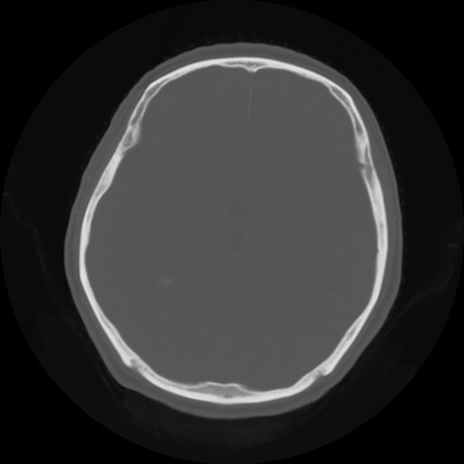

CT(矢状断像)